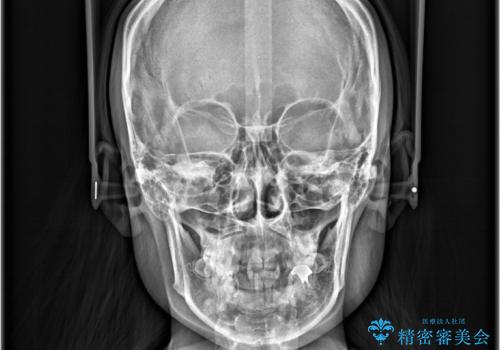

- 「歯のデコボコ、八重歯、口ボコが気になる」を主訴に来院された患者様です。

上下左右4番(4本)の歯を抜歯しワイヤー矯正で治療を行いました。

計4本の抜歯を行い、歯のデコボコと口元がすっきりし、大変ご満足していただけました。